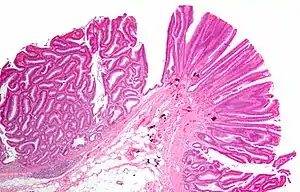

![]() | |

| Tubulovillous adenoma (tubular component – left of image, villous component – right of image). H&E stain. | |